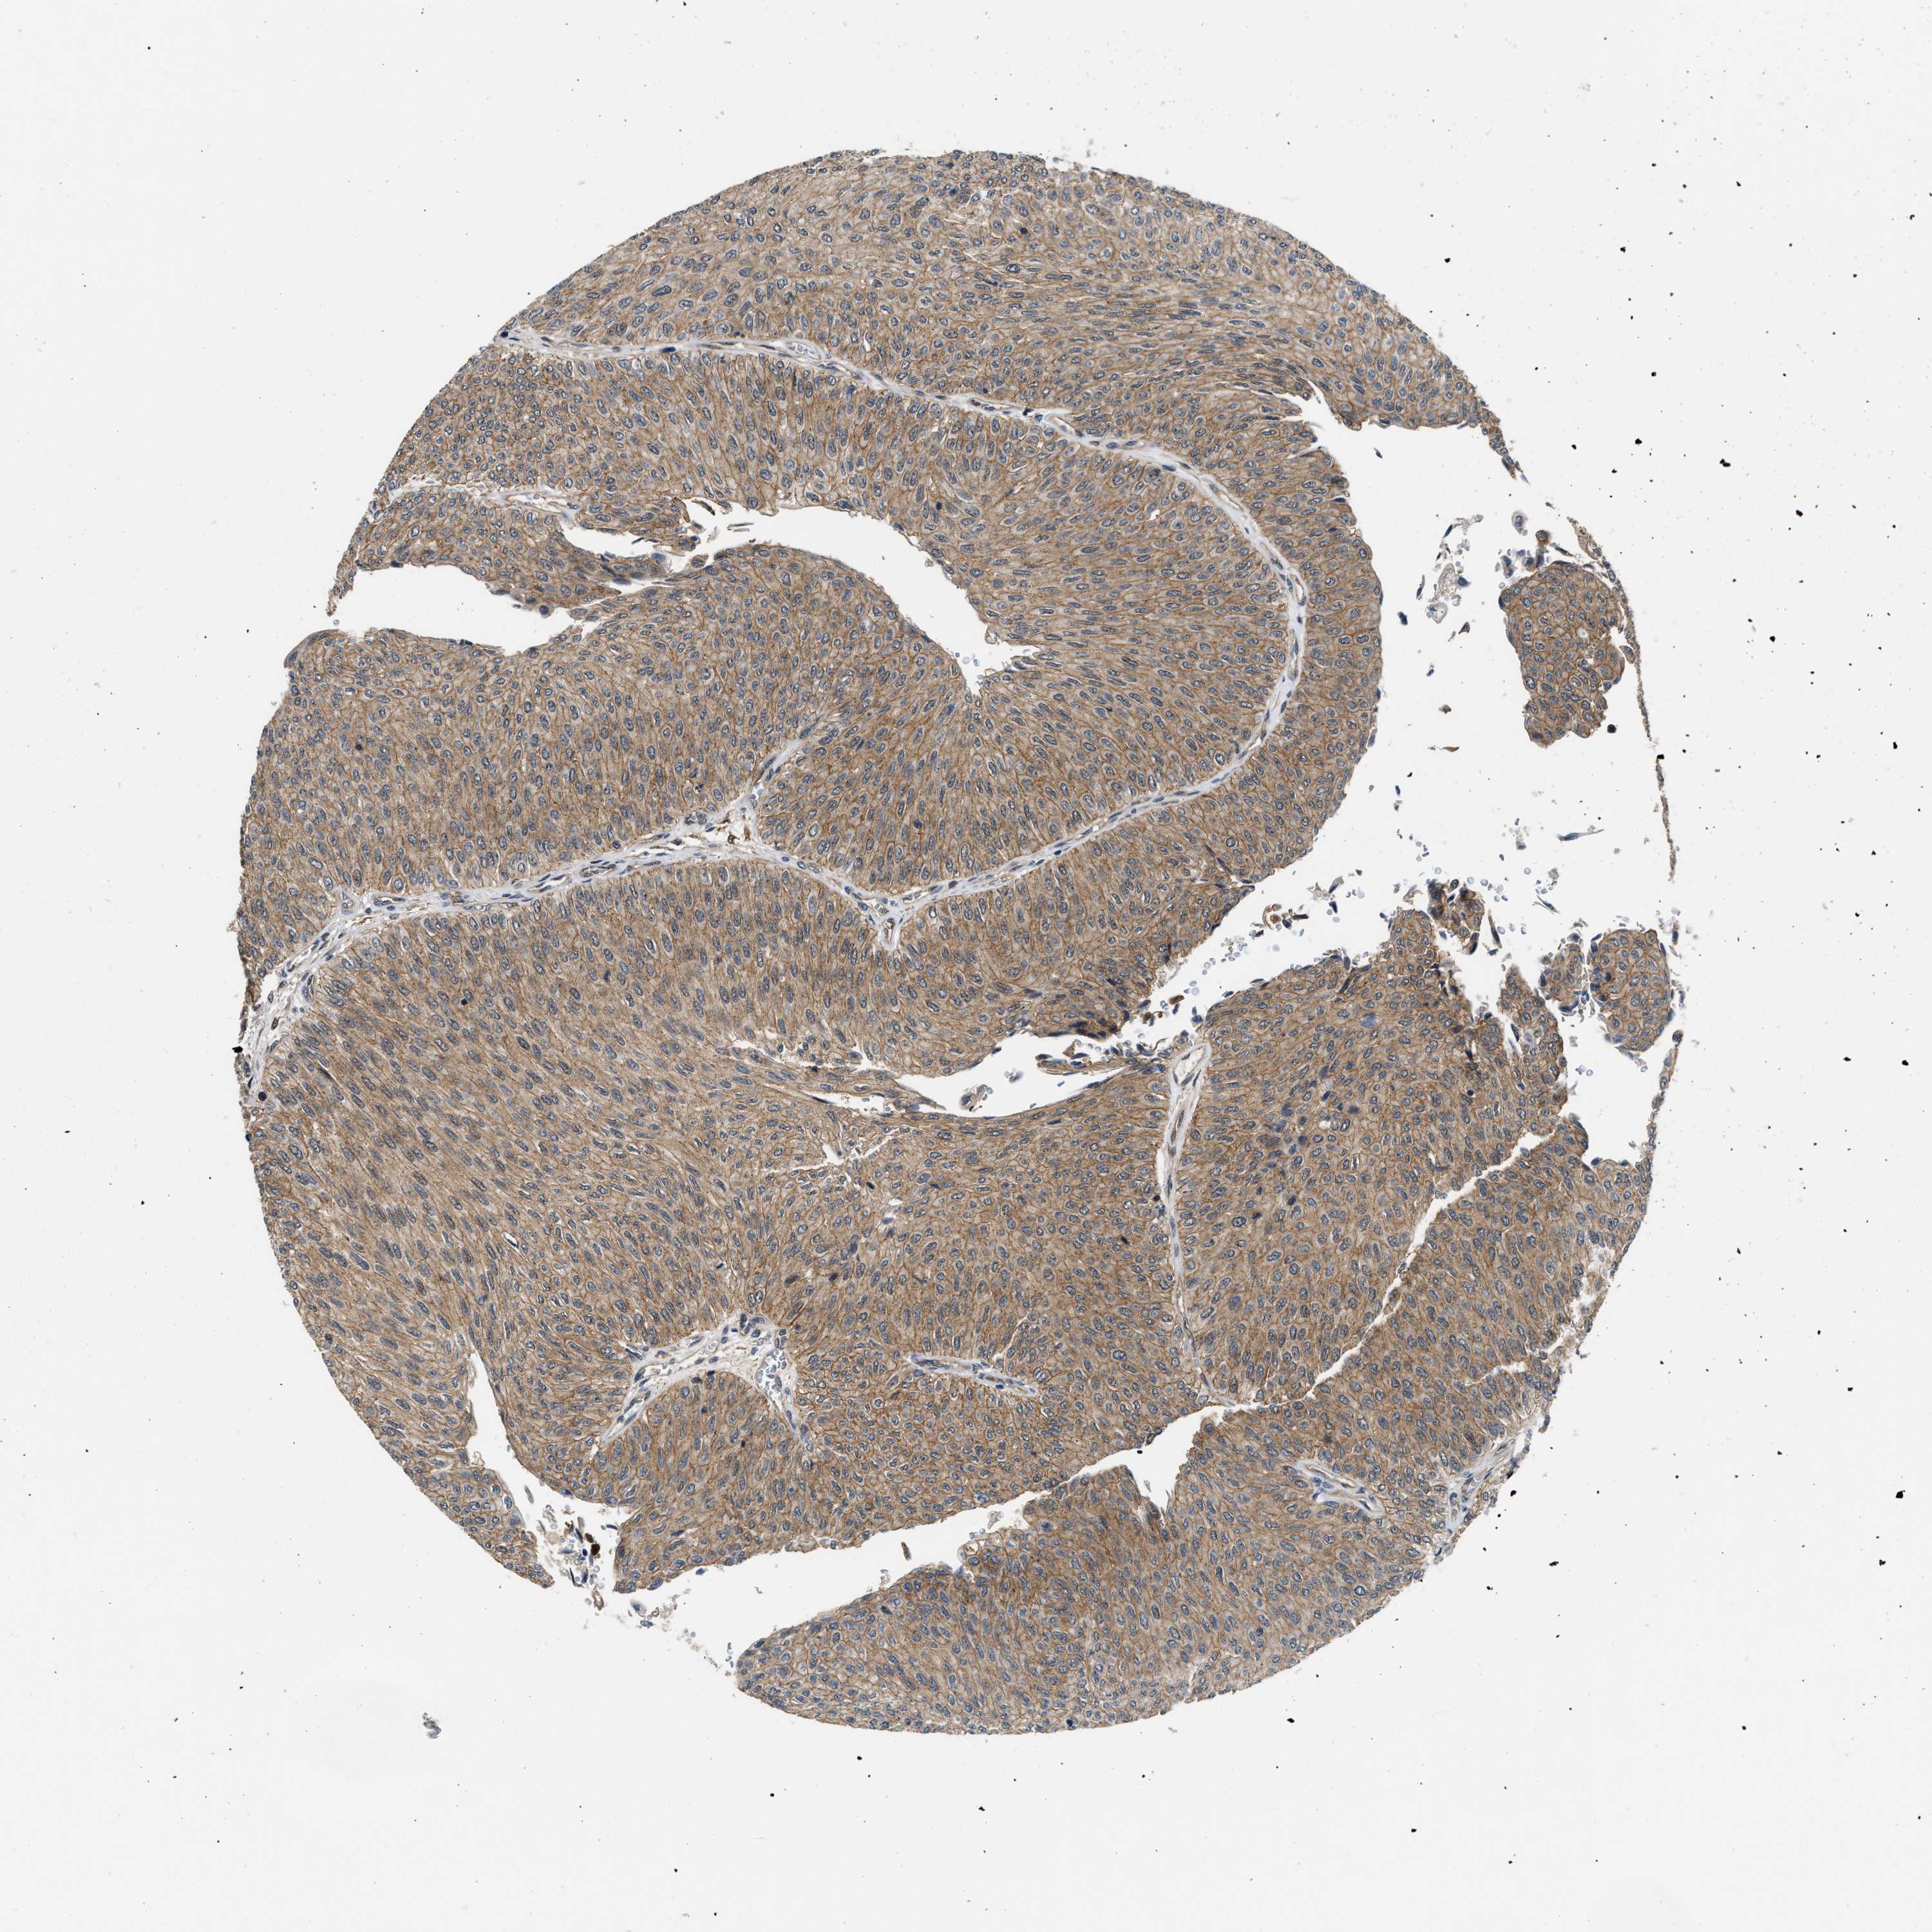

UROTHELIAL CANCER - Protein expressioni

A mouse-over function shows sample information and annotation data. Click on an image to view it in a full screen mode. Samples can be filtered based on level of antibody staining by selecting one or several of the following categories: high, medium, low and not detected. The assay and annotation is described here.

Note that samples used for immunohistochemistry by the Human Protein Atlas do not correspond to samples in the TCGA dataset.

Antibody stainingi

Antibody staining in the annotated cell types in the current human tissue is reported as not detected, low, medium, or high, based on conventional immunohistochemistry profiling in selected tissues. This score is based on the combination of the staining intensity and fraction of stained cells.

Each image is clickable and will lead to virtual microscopy that enables deeper exploration of all samples and also displays staining intensity scores, fraction scores and subcellular localization as well as patient and tissue information for each sample.

Antibody HPA016867

Antibody HPA018271

Urothelial carcinoma, Low grade

Urothelial carcinoma, High grade